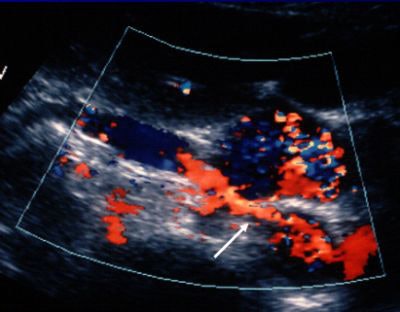

![]() |

| Following administration of ultrasound contrast, a long segmental stenosis with a beaded appearance (arrow) is seen consistent with fibromuscular dysplasia. |